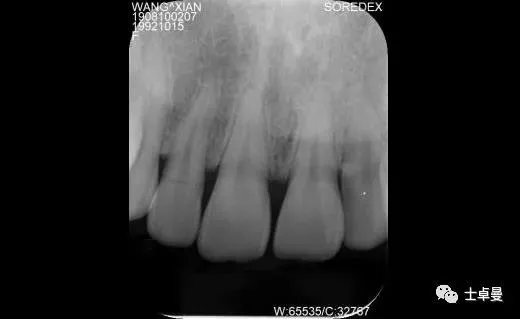

·        CBCT 检查

·       12 断根,根尖区剩余骨高度充足,可用骨高度19mm,骨宽度7.2mm。

术前根尖区显示12折裂

术前 CBCT